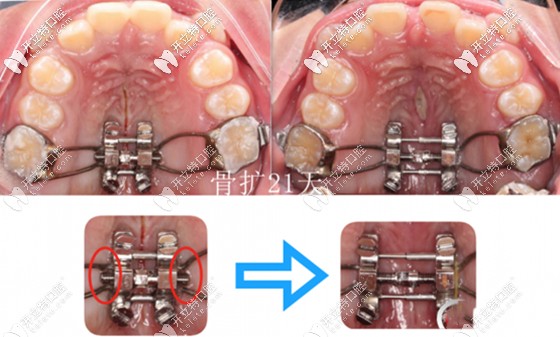

而根據(jù)其擴(kuò)大牙弓的速度不同,可分為快速擴(kuò)弓(周擴(kuò)弓范圍在1.4~3.5㎜)和慢速擴(kuò)弓(周擴(kuò)弓范圍在0. 4~1.2毫米)兩大類。

重點是:快速擴(kuò)弓一般適用于頜面骨骼處于生長發(fā)育期的兒童;而慢速擴(kuò)弓適用于生長發(fā)育已接近完成的大齡青年。

兩者的優(yōu)劣:快速擴(kuò)弓效果快,但維持療效較差;慢速雖然療程較長,不過療效較穩(wěn)定,對牙周組織損傷小。

所以,醫(yī)生多主張慢速擴(kuò)弓矯治,避免欲速則不達(dá)。